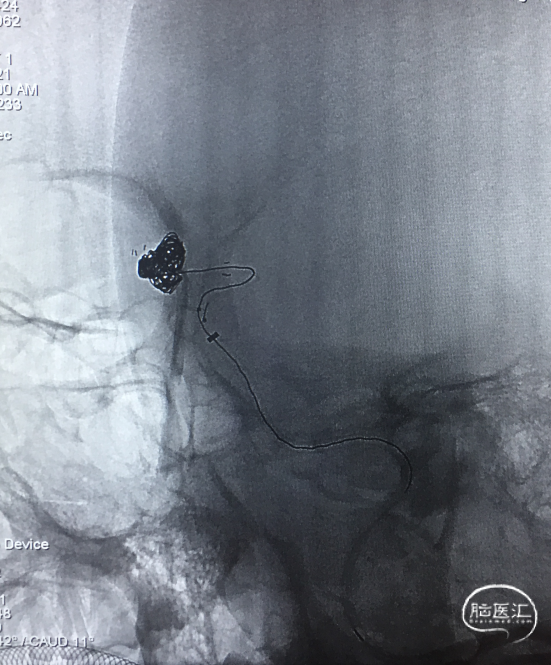

穿网孔超选

将直头SL-10穿过Atlas网眼超选入动脉瘤右侧分叶(左图),蒙片显示Altas形态及双微导管头位置,到达理想位置(右图)。

栓塞过程

直头SL-10及S头SL-10先后交互填圈,分区致密栓塞动脉瘤。